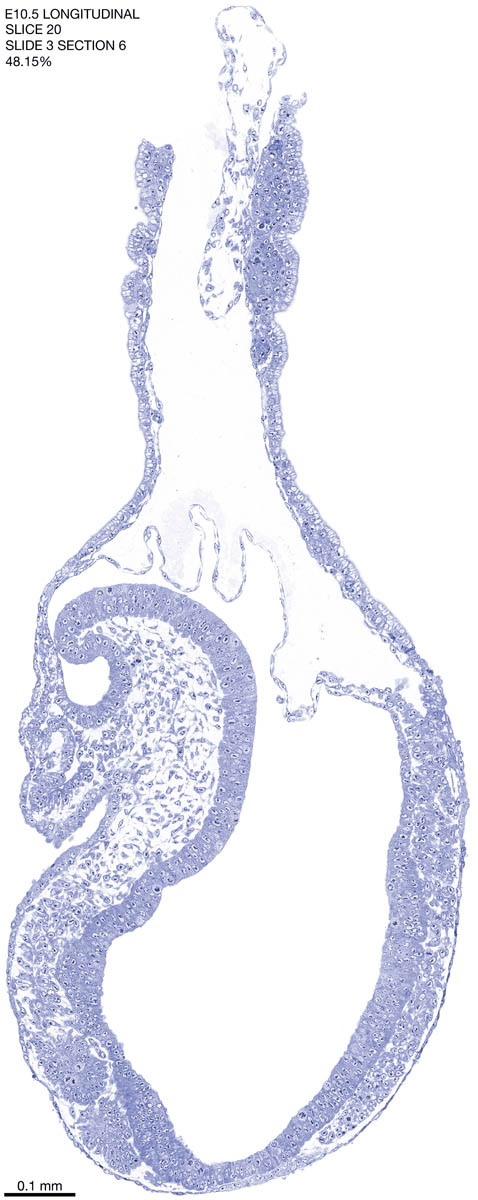

E10.5 Longitudianal Archive This page contains jpg files of ALL SLICES (each 3µm thick) that were scanned of the E10.5 longitudinally cut specimen. Download: Large | High Res Download: Large | High Res Download: Large | High Res Download: Large | High Res Download: Large | High Res Download: Large | High Res Download: Large | High Res Download: Large | High Res Download: Large | High Res Download: Large | High Res Download: Large | High Res Download: Large | High Res Download: Large | High Res Download: Large | High Res Download: Large | High Res Download: Large | High Res Download: Large | High Res Download: Large | High Res Download: Large | High Res Download: Large | High Res Download: Large | High Res Download: Large | High Res Download: Large | High Res Download: Large | High Res Download: Large | High Res Download: Large | High Res Download: Large | High Res Download: Large | High Res Download: Large | High Res Download: Large | High Res Download: Large | High Res Download: Large | High Res Download: Large | High Res Download: Large | High Res Download: Large | High Res Download: Large | High Res Download: Large | High Res Download: Large | High Res Download: Large | High Res Download: Large | High Res Download: Large | High Res Download: Large | High Res Download: Large | High Res Download: Large | High Res Download: Large | High Res Download: Large | High Res Download: Large | High Res Download: Large | High Res Download: Large | High Res Download: Large | High Res Download: Large | High Res Download: Large | High Res Download: Large | High Res Download: Large | High Res Download: Large | High Res Download: Large | High Res Download: Large | High Res Download: Large | High Res